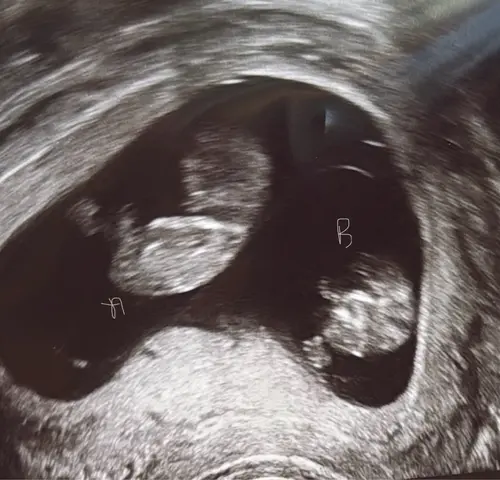

Hoi Dames,

Ik ben ook al een tijdje aan het kijken naar de Nub Theorie methode en o m g … ik kom er gewoon niet uit 🫣 hier zijn jullie een echo foto van mijn tweelingen 🤭 enig idee wat jullie met Nub kunnen zien? Ben benieuwd 🤗 veel succes voor alle aanstaande moeders/ouders 🤍💛